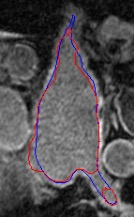

Automated segmentation in medical image analysis is a challenging task that requires a large amount of manually labeled data. However, most existing learning-based approaches usually suffer from limited manually annotated medical data, which poses a major practical problem for accurate and robust medical image segmentation. In addition, most existing semi-supervised approaches are usually not robust compared with the supervised counterparts, and also lack explicit modeling of geometric structure and semantic information, both of which limit the segmentation accuracy. In this work, we present SimCVD, a simple contrastive distillation framework that significantly advances state-of-the-art voxel-wise representation learning. We first describe an unsupervised training strategy, which takes two views of an input volume and predicts their signed distance maps of object boundaries in a contrastive objective, with only two independent dropout as mask. This simple approach works surprisingly well, performing on the same level as previous fully supervised methods with much less labeled data. We hypothesize that dropout can be viewed as a minimal form of data augmentation and makes the network robust to representation collapse. Then, we propose to perform structural distillation by distilling pair-wise similarities. We evaluate SimCVD on two popular datasets: the Left Atrial Segmentation Challenge (LA) and the NIH pancreas CT dataset. The results on the LA dataset demonstrate that, in two types of labeled ratios (i.e., 20% and 10%), SimCVD achieves an average Dice score of 90.85% and 89.03% respectively, a 0.91% and 2.22% improvement compared to previous best results. Our method can be trained in an end-to-end fashion, showing the promise of utilizing SimCVD as a general framework for downstream tasks, such as medical image synthesis and registration.